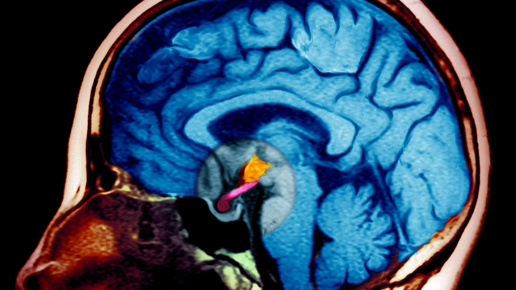

Ядерный магнитный резонанс (ЯМР) – это явление резонансного поглощения радиочастотных волн некоторыми ядрами атомов, размещенных во внешнем магнитном поле. Чаще ЯМР опыты проводят на ядрах атомов водорода, то есть на протонах, или на ядрах изотопа углерода 13 С. На базе ЯМР была развита ЯМР-спектроскопия, позволяющая с великой точностью различать ядер элементов с их свойствами в различном окружении в молекуле. Ядерный магнитный резонанс возникает за счет магнитных свойств ядер. Ядра, которые имеют отличный от нуля спин I, должны также пропорционален него магнитный момент...